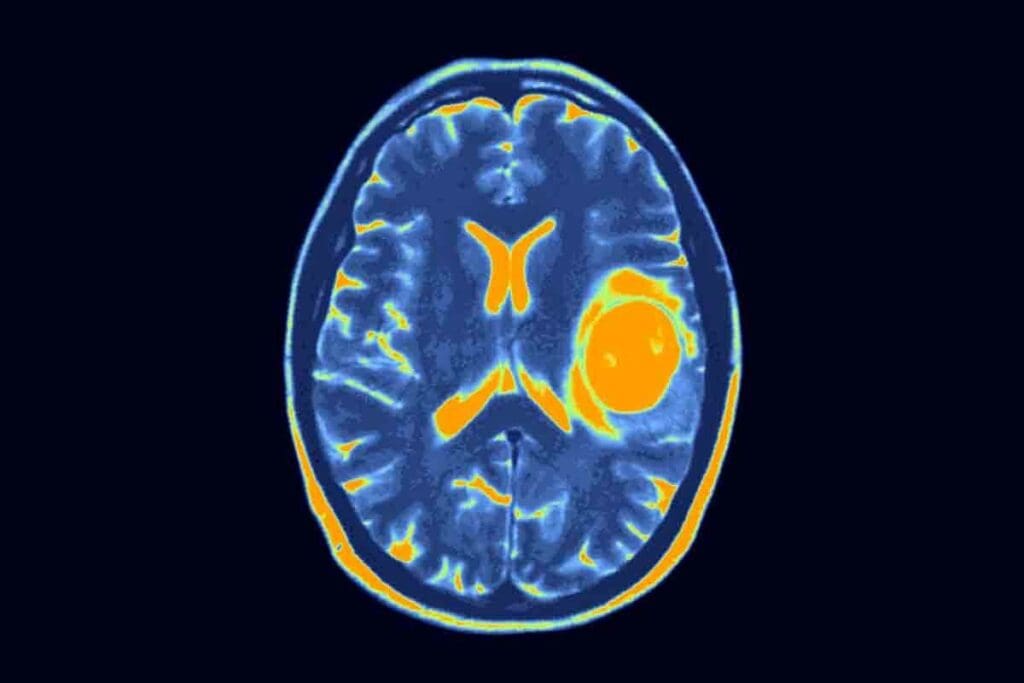

Spotting the early signs of a brain tumor can save lives. These symptoms often seem like normal issues. At Liv Hospital, we focus on both learning and caring for our patients. We look into twelve key signs and personal stories that could change everything. Discover 12 brain tumor early symptoms, how they feel, and when to seek medical help for possible warning signs.

Brain tumors grow in the nervous system or the spinal foramina. Their symptoms depend on the tumor’s location, size, and type. It’s important to know these subtle symptoms for early detection and treatment.